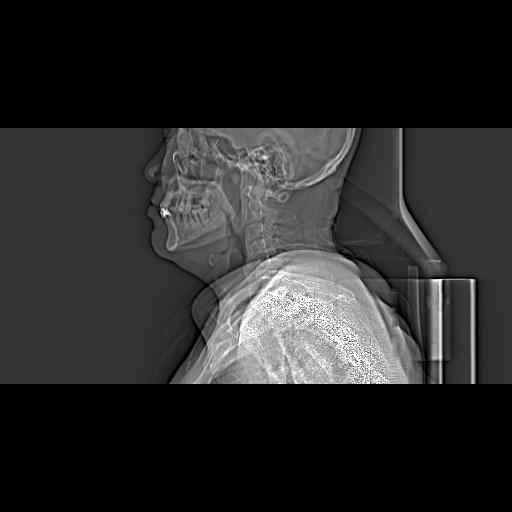

CT51040:扁桃体占位,清大家看看!!

患者,男,78岁。自觉咽喉部进行性加重疼痛3月余,精神尚可。 现ct检查

左侧口咽部可见软组织肿块,部分坏死,左侧咽旁间隙欠清,考虑左侧扁桃体占位---癌可能性大。

考虑左侧扁桃体占位、建议镜检

口咽部新生物,建议行鼻咽纤维镜检查。

左侧扁桃体癌,伴淋巴结转移。建议增强MRI检查!